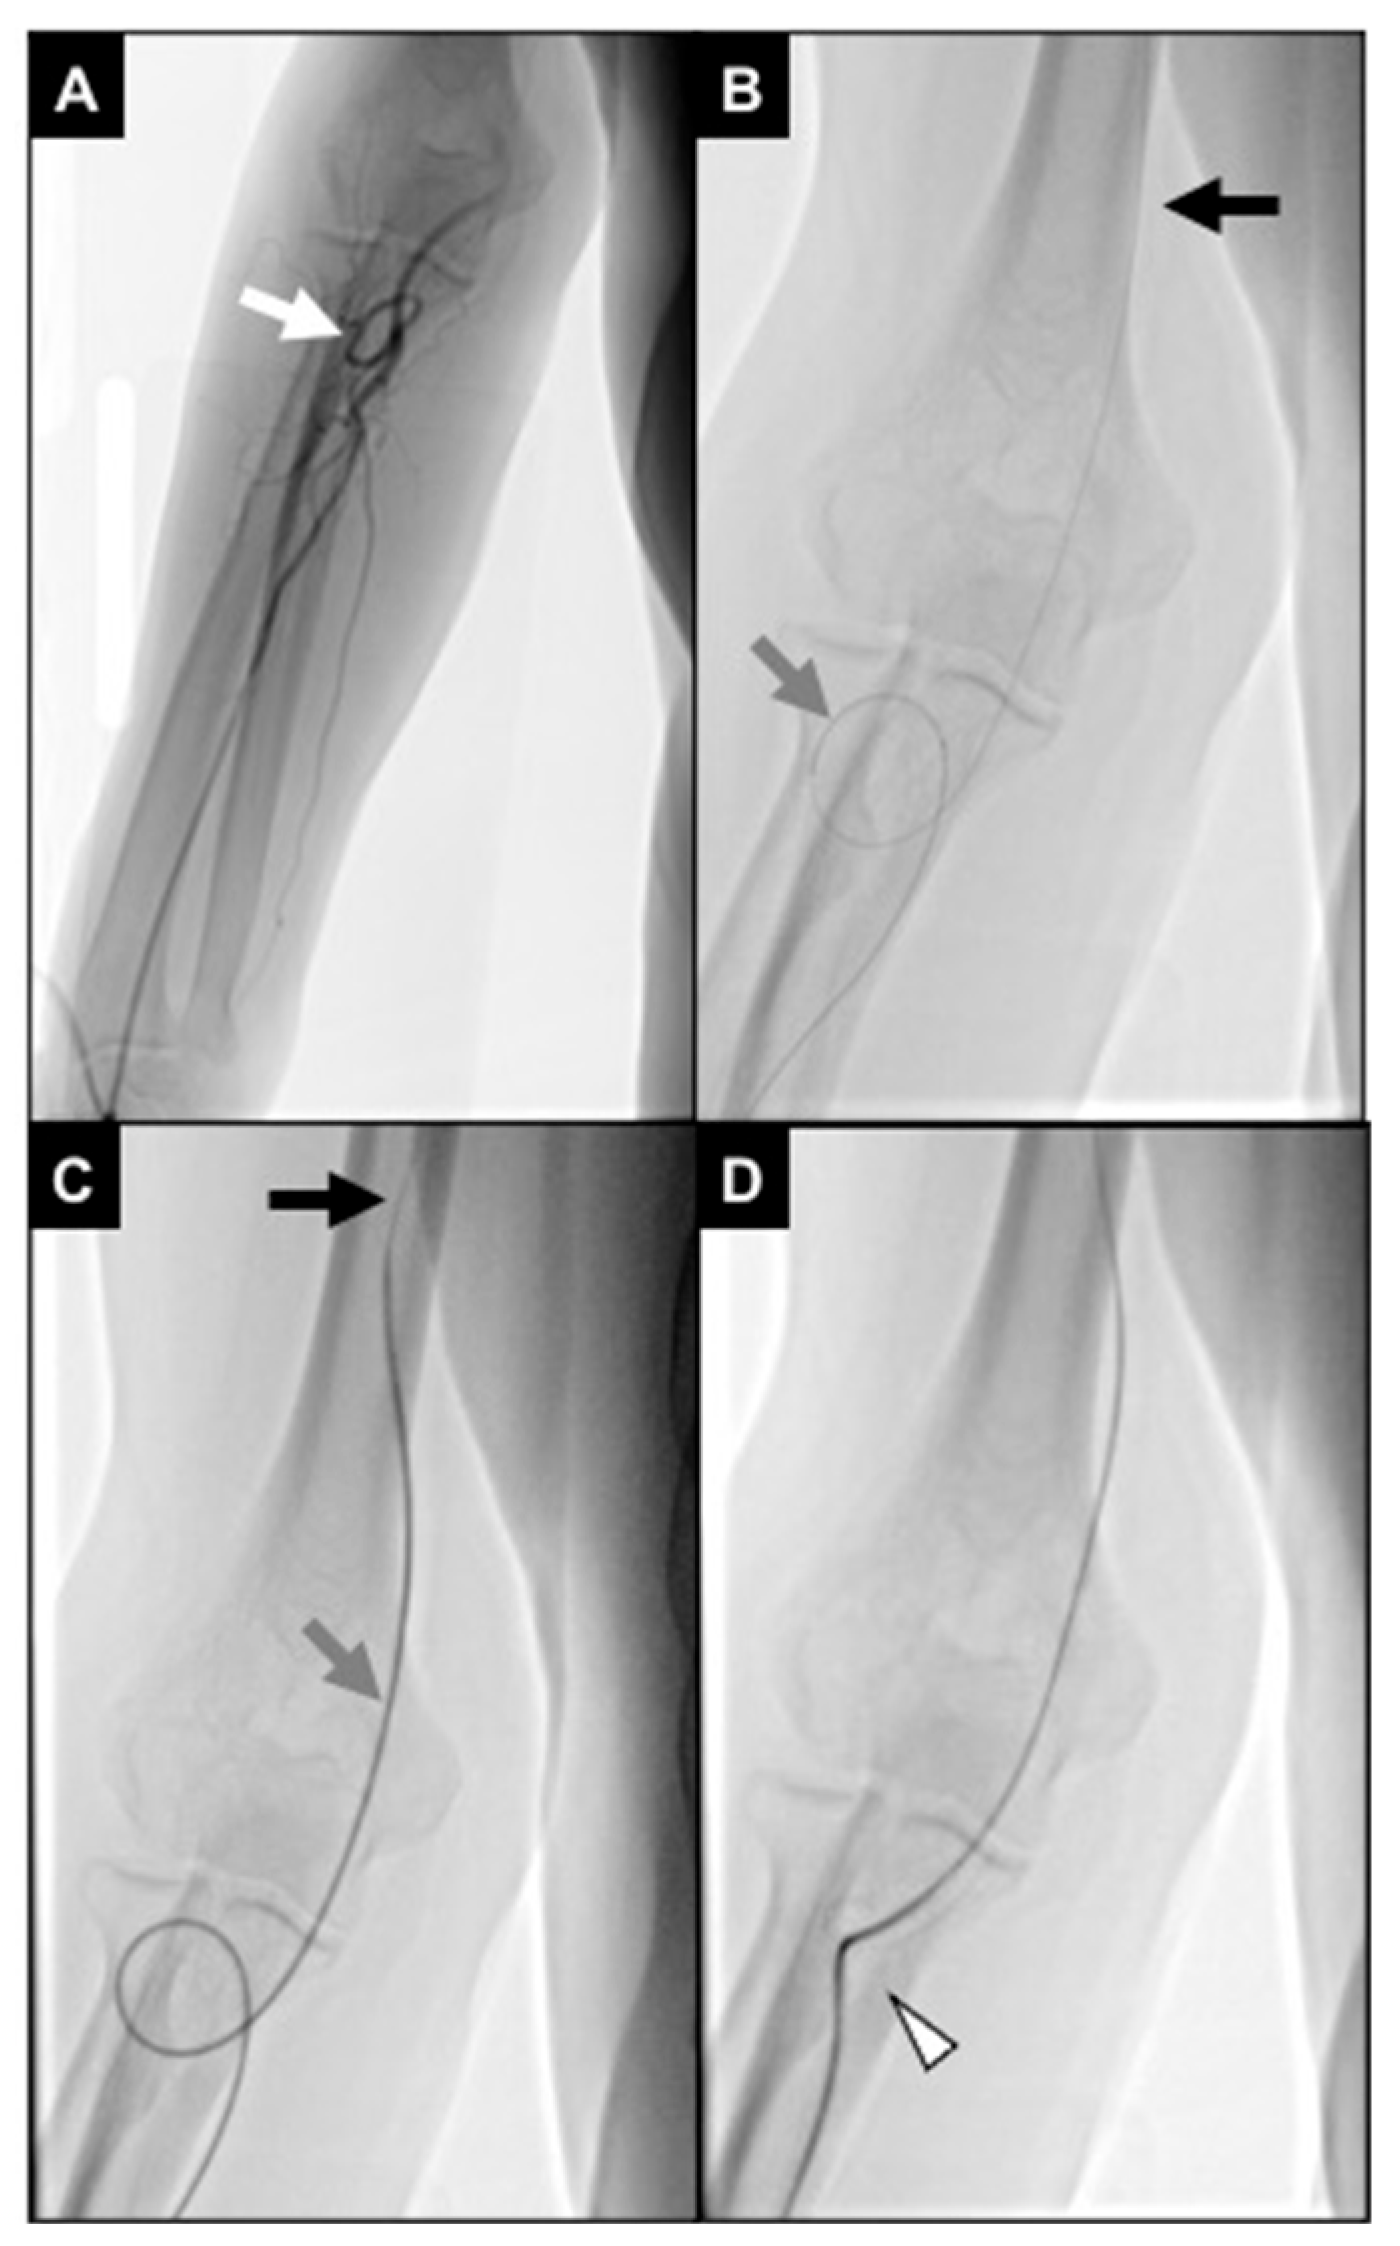

2.4. Procedures